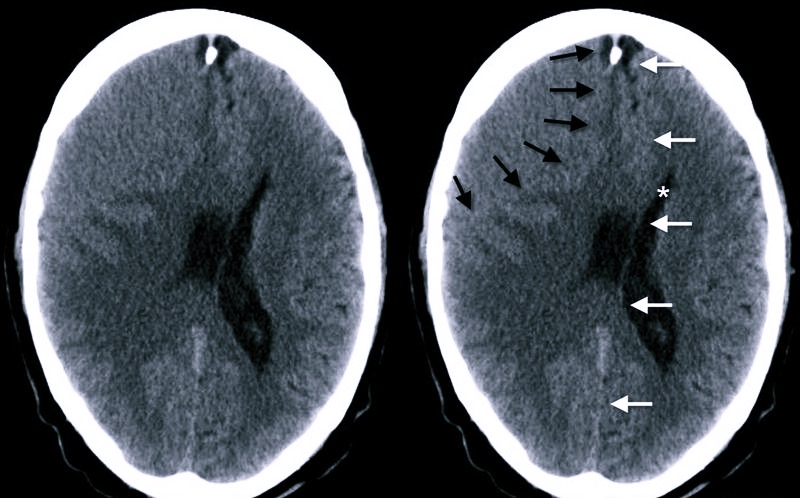

Основными причинами травматического субдурального кровоизлияния является травматизация головного мозга и повреждение интракраниальных вен. Важнейшими диагностическими элементами являются КТ и МРТ, причем современные специалисты больше предпочитают компьютерную томографию, с помощью которой быстро обнаруживается однородная серповидная зона увеличенной плотности.

Спустя некоторое время гематома начинает разуплотняться, распадаются кровяные пигменты, поэтому по уровню плотности через несколько недель после травматизации ее уже сложно отличить от здоровой мозговой ткани. Диагностика в данной ситуации базируется на медиальном смещении латеральных отделов и на обнаружение следов сдавливания бокового желудочка.